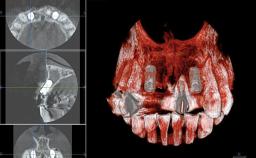

Replacement of Four Incisors with a Fixed Partial Denture on Two Narrow-Neck Implants after Implant Failure

| Jaw | Maxilla |

| Area | Anterior |

| # of Implants | 2 |

| Type of Implants | One-Piece|Reduced-Diameter |

| Bone Volume | Deficient vertically or deficient vertically AND horizontally |

| Anatomic Risk | High |